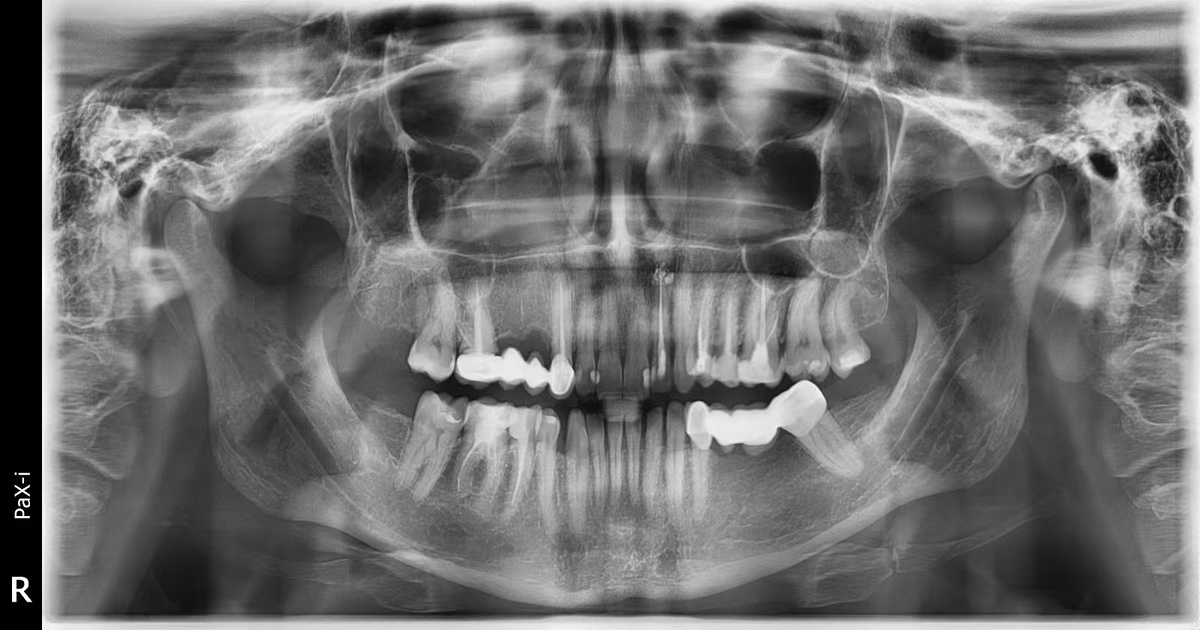

В идеале всё выглядит так: вы проходите лечение у себя дома. Вылечиваете каналы, снимаете старые мосты, удаляете всё, что не подлежит восстановлению. Через 2–3 недели делаете панорамный снимок. Присылаете его нам. Мы его анализируем. Честно говорим: готовы вы или нет. Если всё хорошо — вы приезжаете в Хэйхэ, и за 3–4 дня получаете полностью новое протезирование. С красивыми коронками, с точной прикусной линией, с CAD/CAM-технологией, с гарантией от государственной больницы.

Как выглядит ОПТГ снимок.

Мы принимаем пациентов только с подготовкой. Только по снимку. Только тогда, когда можем гарантировать результат. Мы не играем с зубами. Мы их восстанавливаем так, чтобы вы потом забыли, что они когда-то были проблемой.